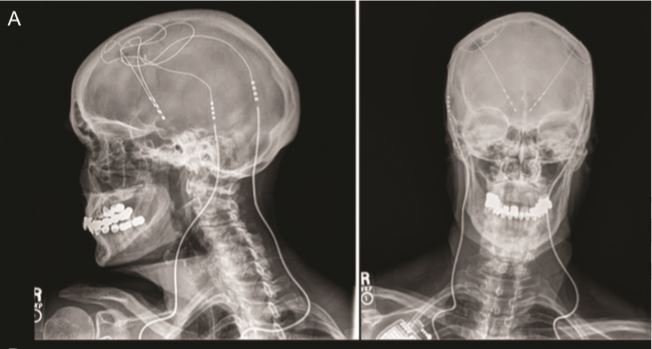

The small study involved three patients with Alzheimer's disease who had a deep-brain-stimulation (DBS) device implanted in their frontal lobe — a part of the brain tied to "executive functions," which include planning, problem-solving, attention and judgment. The implant, sometimes called a "brain pacemaker," consists of thin electrical wires connected to a battery pack that sends electrical impulses into the brain.

In the new study, DBS implants were placed in a part of the frontal lobe called the ventral striatum. Participants periodically completed a test intended to measure aspects of cognitive function that are affected by Alzheimer's disease, including executive functioning and the ability to carry out basic daily activities. The participants with the implants were compared to a group of about 100 people with Alzheimer's disease who were around the same age and had similar levels of cognitive impairment, but did not receive DBS.